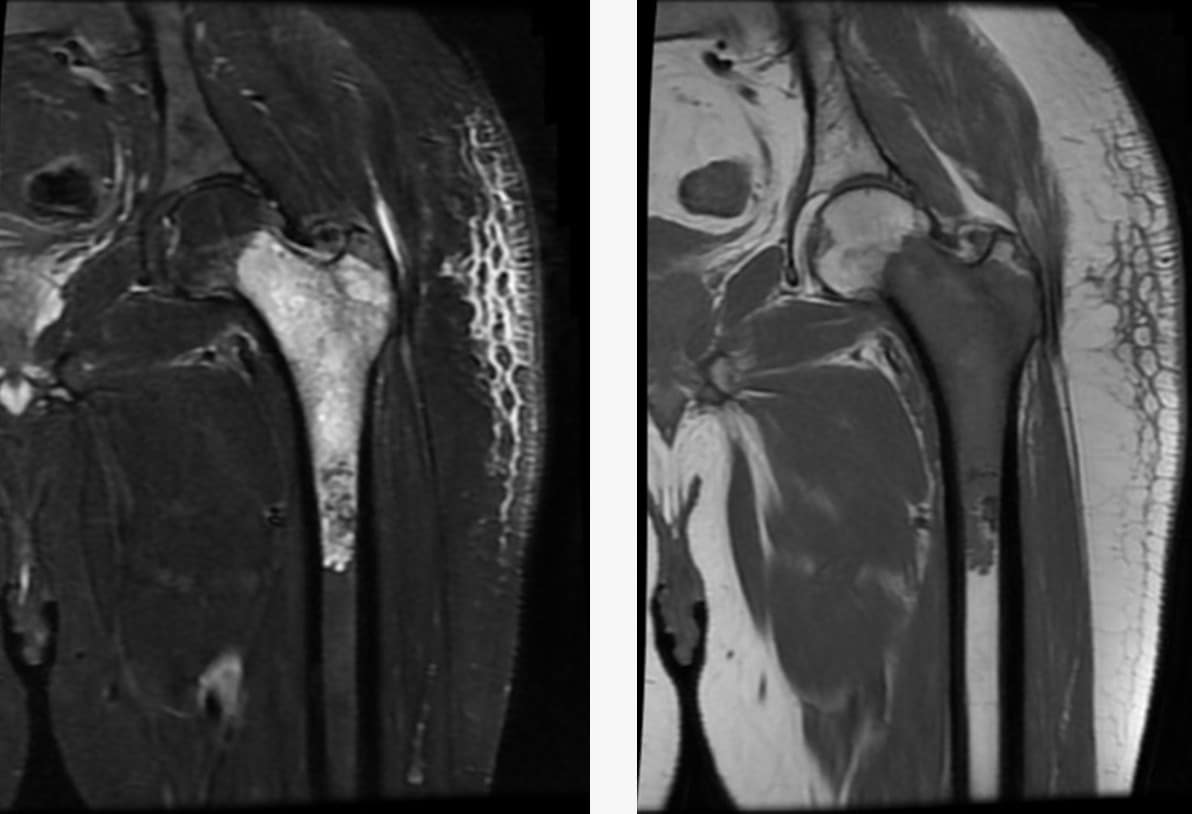

Not anymore. With advancements in technology and “Limb Salvage Surgery,” roughly 90-95% of patients can save their limbs. We remove the tumor and reconstruct the bone using metal implants or bone grafts, preserving both the appearance and function of the limb. For more details visit Dr. Pradeep.